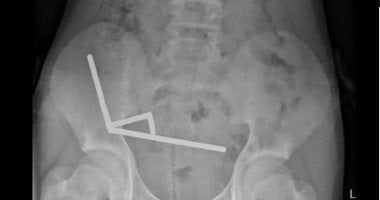

المغناطيسات المستخرجة من بطن المراهق

وقال المسؤولون، إن المغناطيسات التي تم حظرها فى منذ يناير2013 تم شراؤها من منصة للتسوق عبر الإنترنت تيمو، وأظهرت الأشعة السينية أن المغناطيسات قد تكتلت في أربعة خطوط مستقيمة داخل أمعاء الطفل، وبدا أنها فى أجزاء منفصلة من الأمعاء ملتصقة ببعضها البعض بفعل القوى المغناطيسية.